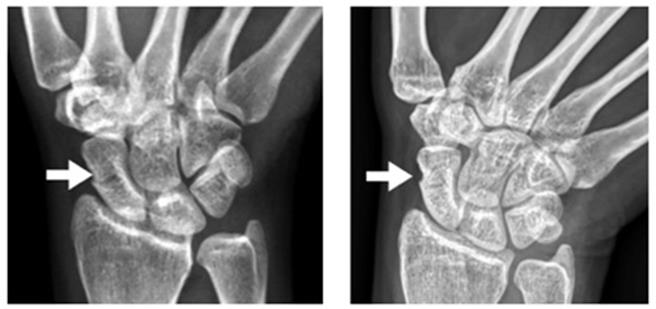

35岁的彭小姐因骑车上班途中不慎擦撞,造成手部撑地挫伤肿痛,因无明显其他外伤,且肿痛感还可忍受,所以不以为意仍继续骑车,但数天后发现肿痛并无消退,故至新竹台大分院生医医院竹北院区骨科部就医,经由X光检查,诊断是腕部的舟状骨骨折,很幸运地骨折处为癒合率较高的舟状骨中段,且无明显移位,经与病人说明后,接受两个月石膏保护治疗,症状顺利改善,且X光可以看出骨头明显癒合。

李育成解释,舟状骨中段及远端的非移位性骨折,可藉由石膏包覆治疗得到妥善结果,如案例中的彭小姐在经由近两个月治疗后,藉由X光可看出病人骨头明显癒合。此外,较复杂的舟状骨骨折也可藉由手术復位和加压螺钉的固定方式,增加舟状骨骨折的稳定性,并于术后配合石膏保护,降低后续产生併发症的机率。李育成建议,如于明显外伤事件后,有感到迟未恢復的腕部局部疼痛,建议就医检查,接受适当的治疗。